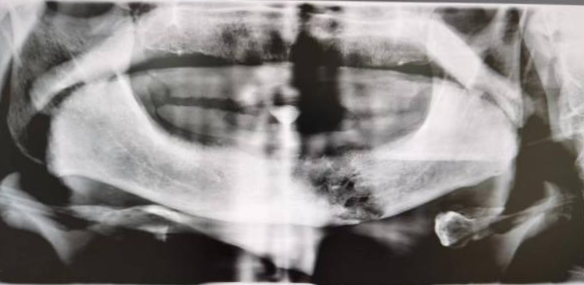

牙齿由于龋坏等原因而致使牙冠的大部分缺损,仅剩余牙根,称为残根。那这样的“烂牙根”能否放任自流不治不拔呢?答案是否定的。残根长期留在口腔有哪些隐患呢?下面马医生一一跟大家分享。

•残根的保留和拔除•

一般情况下,残根缺损到牙龈下不超过3mm,牙根有足够的长度,牙槽骨没有吸收,通常可以尝试保留做桩核冠修复或覆盖义齿等;如果残根缺损到牙龈下超过3mm,或磨牙已经破坏髓室底,通常建议及时拔除,及时修复。当然残根的处置医生还要结合患者的意愿来决定。残根保留治疗或者拔除镶牙都会花费更多的时间和费用,因此牙齿出现龋洞一定要尽早补起来,日常应认真仔细的刷牙,定期做口腔检查,维护口腔健康!